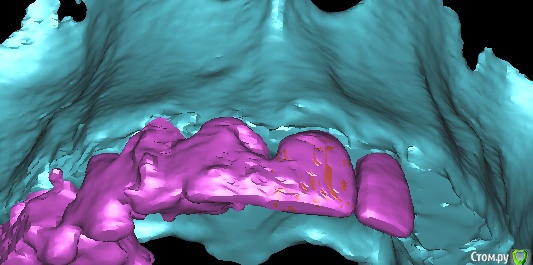

x4ex Опубликовано 16 октября, 2017 Автор Поделиться Опубликовано 16 октября, 2017 Графта не было. Насчёт удаления зуба не помню, возможно даже там первичная адентия была.Девушке 27лет и она пришла с коронкой на 12 с консолью на 11. КТ до есть, после только прицельный. Завтра всё добавлю. Имплант ставил субкрестально, примерно на 2мм, исходя из положения зенита соседнего зуба. Ссылка на комментарий

колесников Опубликовано 16 октября, 2017 Поделиться Опубликовано 16 октября, 2017 Все ещё есть вопрос к позиции импланта и его диаметру. Предположу что был 4.1 и позиция вестибулярная,плюс добавим скелетирование вестибулярно. Ссылка на комментарий

x4ex Опубликовано 17 октября, 2017 Автор Поделиться Опубликовано 17 октября, 2017 Подозрительно не то слово. Клянётся, что проходит каждый год медосмотры и никаких патологий выявлено не было.Не знаю, как изменить шапку, поэтому добавлю снимки сюда. Ссылка на комментарий